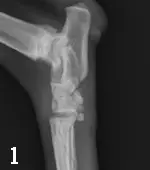

Left tarsal radiographs: Lateral and dorsoplantar (DP) views

Radiographic Findings (Figures 1 and 2):  There is an oblique fracture of the proximal diaphysis of the 2nd metatarsal bone with minimal displacement. There is displacement of all metatarsal bones dorsally relative to the distal row of tarsal bones. This is best visualized in the lateral view. In addition, there is also increased joint space in the tarso-metatarsal joint, which is more severe medially. The first metatarsal bone is a small rounded opacity superimposed over the abnormally widened joint space in the DP view; this should not be confused with a fracture fragment.

Diagnosis (Figure 3): These findings indicate a fracture of the 2nd metatarsal bone (arrow) and, more importantly, subluxation of the tarso-metatarsal articulation (arrowhead). In human medicine, this is called a Lisfranc injury and is most commonly identified in athletes.